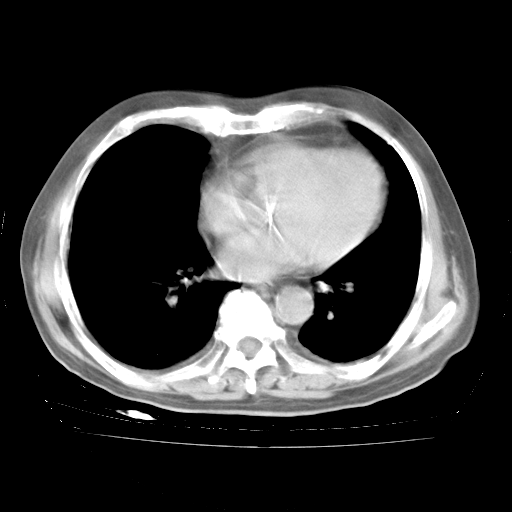

4月28日肺部CT——再次出现类似去年5月9日——透光度降低,“间质性”改变。

4月28日肺部CT——再次出现类似去年5月9日——磨玻璃样、间有“粟粒样”改变。

4月28日肺部CT

个人阅读4.14日肺部CT平扫:纵隔窗无异常,但肺窗示:双下肺内、后基底段有片絮状侵润影,部位以后基底段为著,以间质改变为主,呈急性肺泡炎征像,和首次住院影像学有相似之处。仅是个人读片,明日请相关专家再读片哈。其它建议同上。

1、108#的是4月14日的胸部CT(发此贴时还没看着28日的CT)。14日的胸部CT其实已经出现改变(如108#所述),个人认为28日的胸部CT除纵膈窗疑似有双侧胸膜增厚或少量胸积液(可行胸部B超明确)外,与4月14日对照病变有所加重;2、已经给予“异烟肼、利福平、乙胺丁醇”抗痨治疗?如果是,甲强龙80mg可缓慢减量;如果环磷酰胺已停用,暂不使用;3、中性粒细胞92%,明显升高,目前体温情况?注意合并细菌感染可能,使用左氧氟沙星情况下,是否联用B-内酰胺类抗菌药物?另外是查免疫全套非风湿全套。

今请临免主任会诊后认为:4月14日胸部CT已有双下肺间质性改变。患者病情复发多系激素减量过快不正规所致。目前甲强龙80mg/日,一周后酌情开始减量,不易过快。环磷酰胺若已停用,暂不使用。他同意目前抗菌药物使用,但应考虑是否加用B-内酰胺类抗菌药物(中性细胞明显增高);2、结核复发目前依据不足;3、若免疫全套各项指标正常,考虑多系特发性肺间质炎可能大。4、加强支持,并注意保护胃黏膜。

今上午去请教了临免、呼吸主任:1、介绍病史和阅读系列胸部CT一致认为:患者肺结核不考虑,仍为肺间质纤维化,目前处于急性肺泡炎阶段。2、若仍发热,可将甲强龙增至:80mg Bid静滴,同时鉴于中性增高,合并细菌感染可能,继续左氧氟沙星治疗,再联用B-内酰胺抗菌药物,如头孢哌酮--舒巴坦;3、停用抗痨药;4、目前甲强龙每日剂量160mg ,体温正常后再酌情减量;目前暂不用免疫抑制剂;4、不建议使用免疫增强剂等;5、加强支持治疗,鼓励患者进食;5、注意随访肝、肾功及血常规情况;6、因患者目前激素用量较大,加用胃黏膜保护剂,防止消化道出血可能。